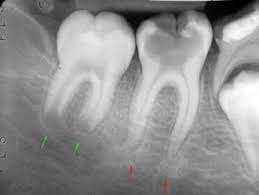

ASPECTO RADIOLOGICO DE LA CARIES

CARIES RECURRENTES

•          Se presenta adyacente a una restauración preexistente debido a una preparación inadecuada de la cavidad

•      Se radiolucida, por debajo de una restauracio